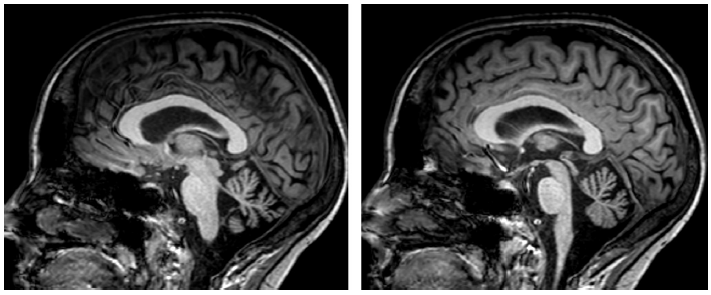

图4显示的是全身免疫疾病相关的小脑萎缩。特异的影像学征象,如T2加权图像中脑干周围的低信号边缘,见于表面铁沉积症(图 5)。

图 4 自身免疫性多内分泌腺综合征相关的小脑萎缩。左:头颅MRI T1加权序列矢状位影像显示蚓部萎缩。右:头颅MRI T2加权序列冠状位图像显示小脑沟增大。

切除原发性肿瘤后,不可逆的小脑后遗症很常见,结构成像可清楚地显示其程度(图 6)。

图 6 手术切除室管膜瘤后小脑和脑干的后遗症。图为头颅MRI T1加权序列图像。

同时存在小脑性共济失调和自主神经功能障碍的主要原因是多系统萎缩(图 7),典型表现是桥脑出现“十字征”(图 8)。

图7 小脑型多系统萎缩。头颅MRI T1加权序列矢状位图像显示明显的小脑萎缩。